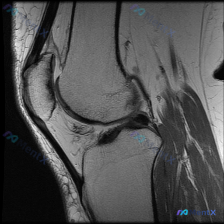

核心问题:临床怀疑膝关节存在软骨异常,提供单张膝关节矢状位MRI,请分析图像中的明显发现。

这是一张清晰度良好的膝关节矢状位PD/T2加权MRI,左侧为前(髌骨侧),右侧为后,上方为股骨远端,下方为胫骨近端,对比度适中,解剖结构显示清晰,无明显伪影,符合膝关节常规检查序列特征。

- 骨骼与骨髓:股骨远端、髌骨、胫骨近端骨皮质连续,无骨折线,骨髓信号均匀,无骨髓水肿

- 关节软骨:股骨滑车及胫骨平台关节软骨显示清晰,边缘光整,未见软骨缺损、变薄或剥脱

- 半月板:形态自然,边缘锐利,低信号均匀,无高信号延伸至表面,排除明显撕裂

- 交叉韧带:前后交叉韧带走行自然,连续性良好,信号无异常

- 肌腱与脂肪垫:髌腱走行厚度正常,无异常信号;髌下脂肪垫形态正常,无水肿或占位

- 关节囊:髌上囊及关节间隙无异常液体积聚